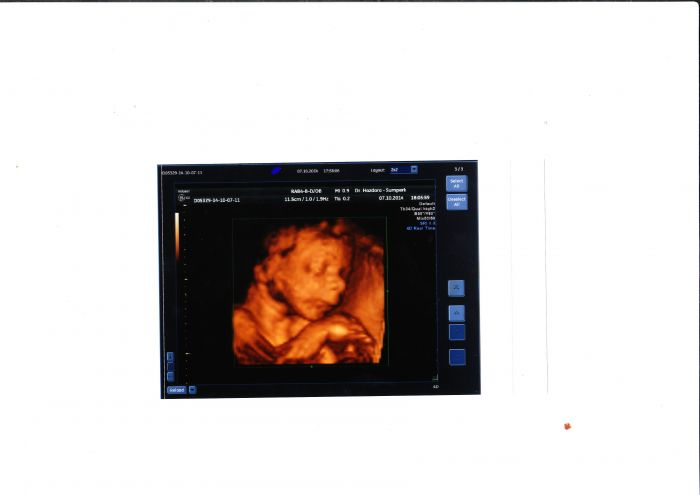

Děvčata,včera jsem byla na 4Dultrazvukovém záznamu...dala jsem za to sice 1000kč,ale to dvd(zkouknu dnes bez nastávajícího tatínka-pro něj to bude překvápko) a fotky stojí za to!!! Posílám malou ochutnávku..a přeji krásný den všem

[647928] Jee ty jsou krasny,to bude tatka koukat :) jak si tam lebedi vid ;)